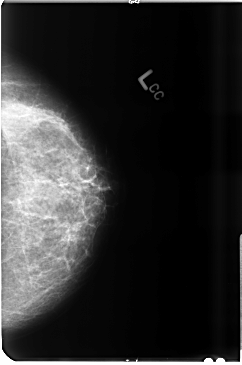

B_3491_1.LEFT_CC

LEFT_CC LINES 4736 PIXELS_PER_LINE 3136 BITS_PER_PIXEL 12 RESOLUTION 50 NON_OVERLAY